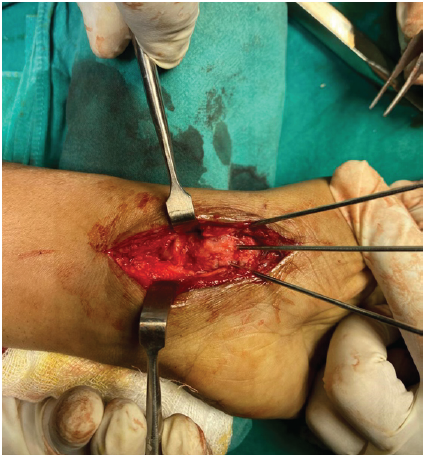

Patient positioned supine on OT table with arm on side table and under unsterile tourniquet with pressure 220 mm of Hg skin incision taken over previous incision site under all aseptic precautions, after exposing the fracture site gross non-union (Fig. 2) along with osteomalacia of proximal pole of scaphoid (Fig. 3) and large bone defect was found which could not be addressed with simple bone grafting.

Figure 2: Clinical non-union site.